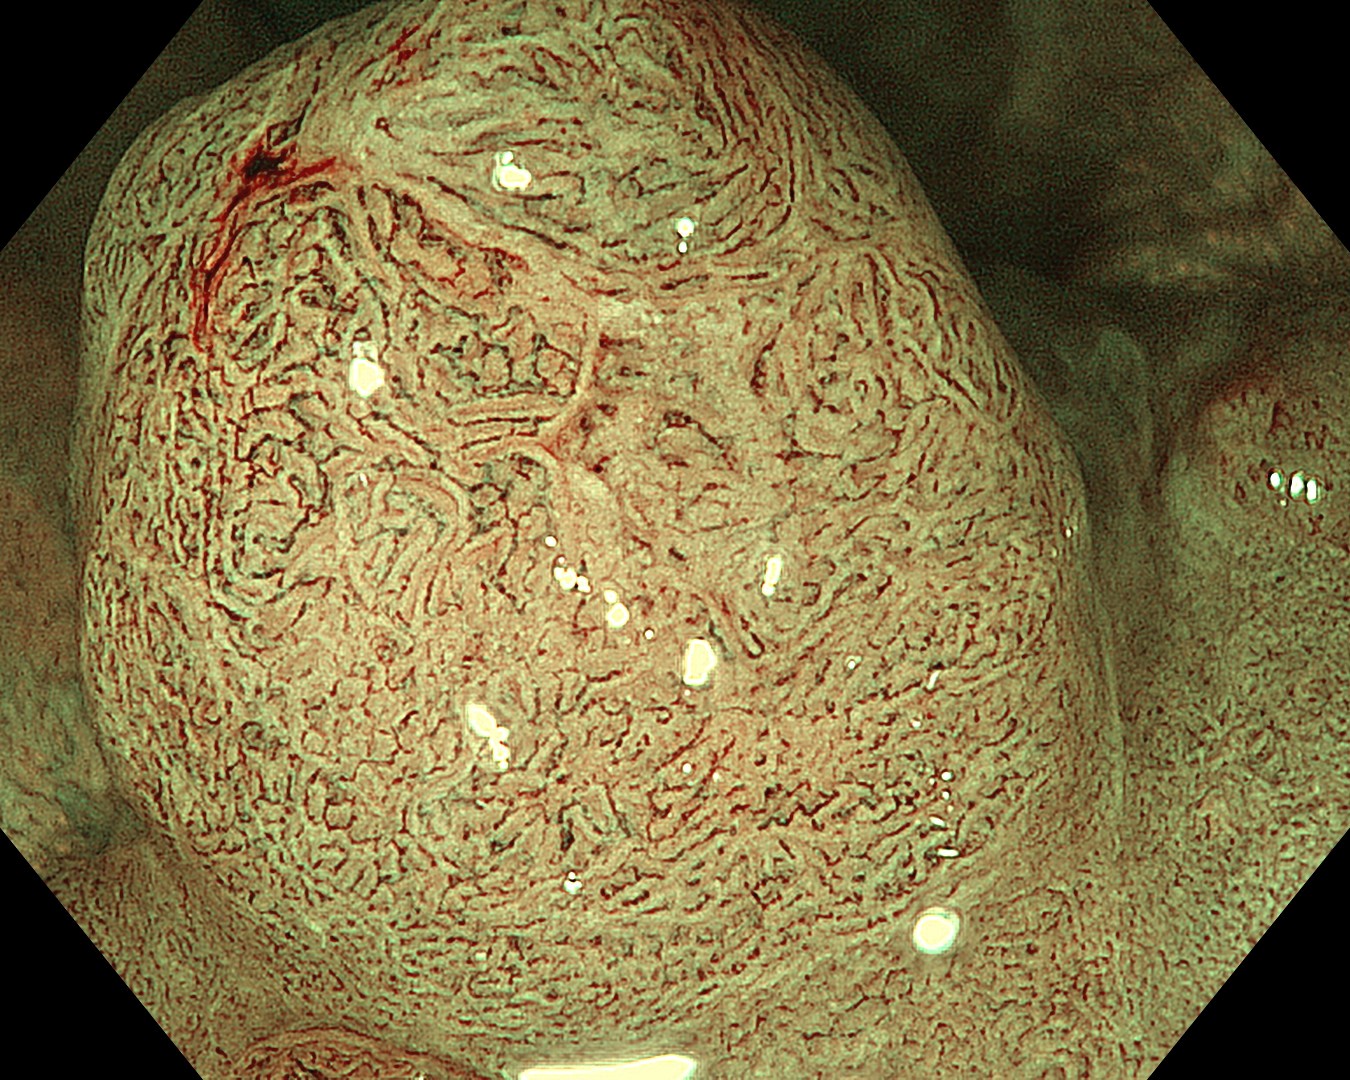

• NBI観察③(拡大)

強調設定:B8

図5

関心領域周囲では、表面構造・血管走行ともに不整で、Vessel Pattern・Surface PatternともにJNET type 2Bの所見であった。一方、関心領域では、表面構造・血管走行ともに不明瞭であり、JNET type 3も否定できない所見であった。